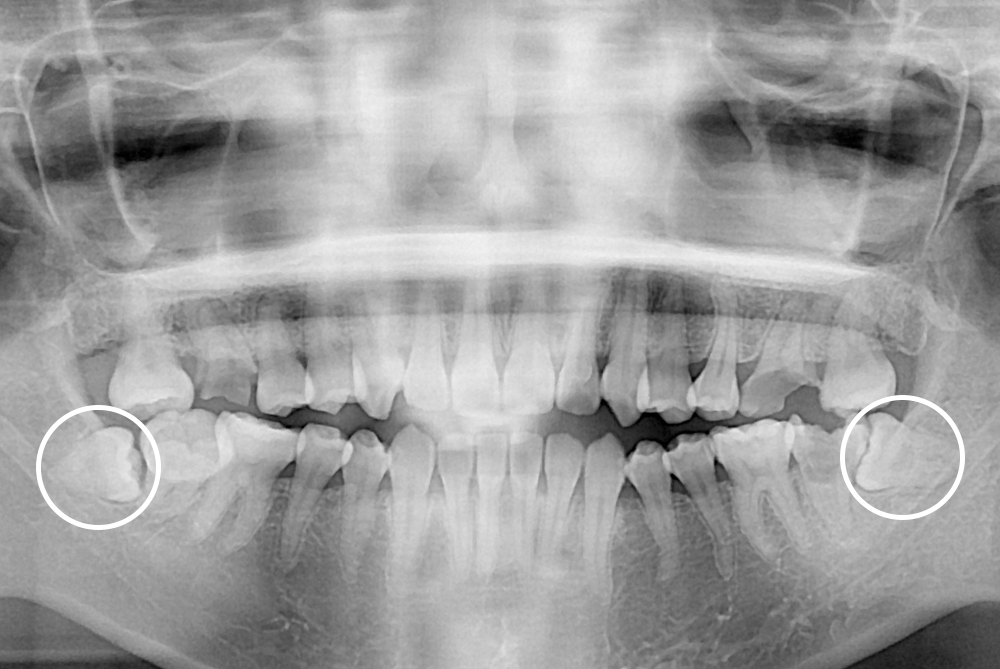

[사랑니] 매복 사랑니 발치

치료전 : 2019-09-10